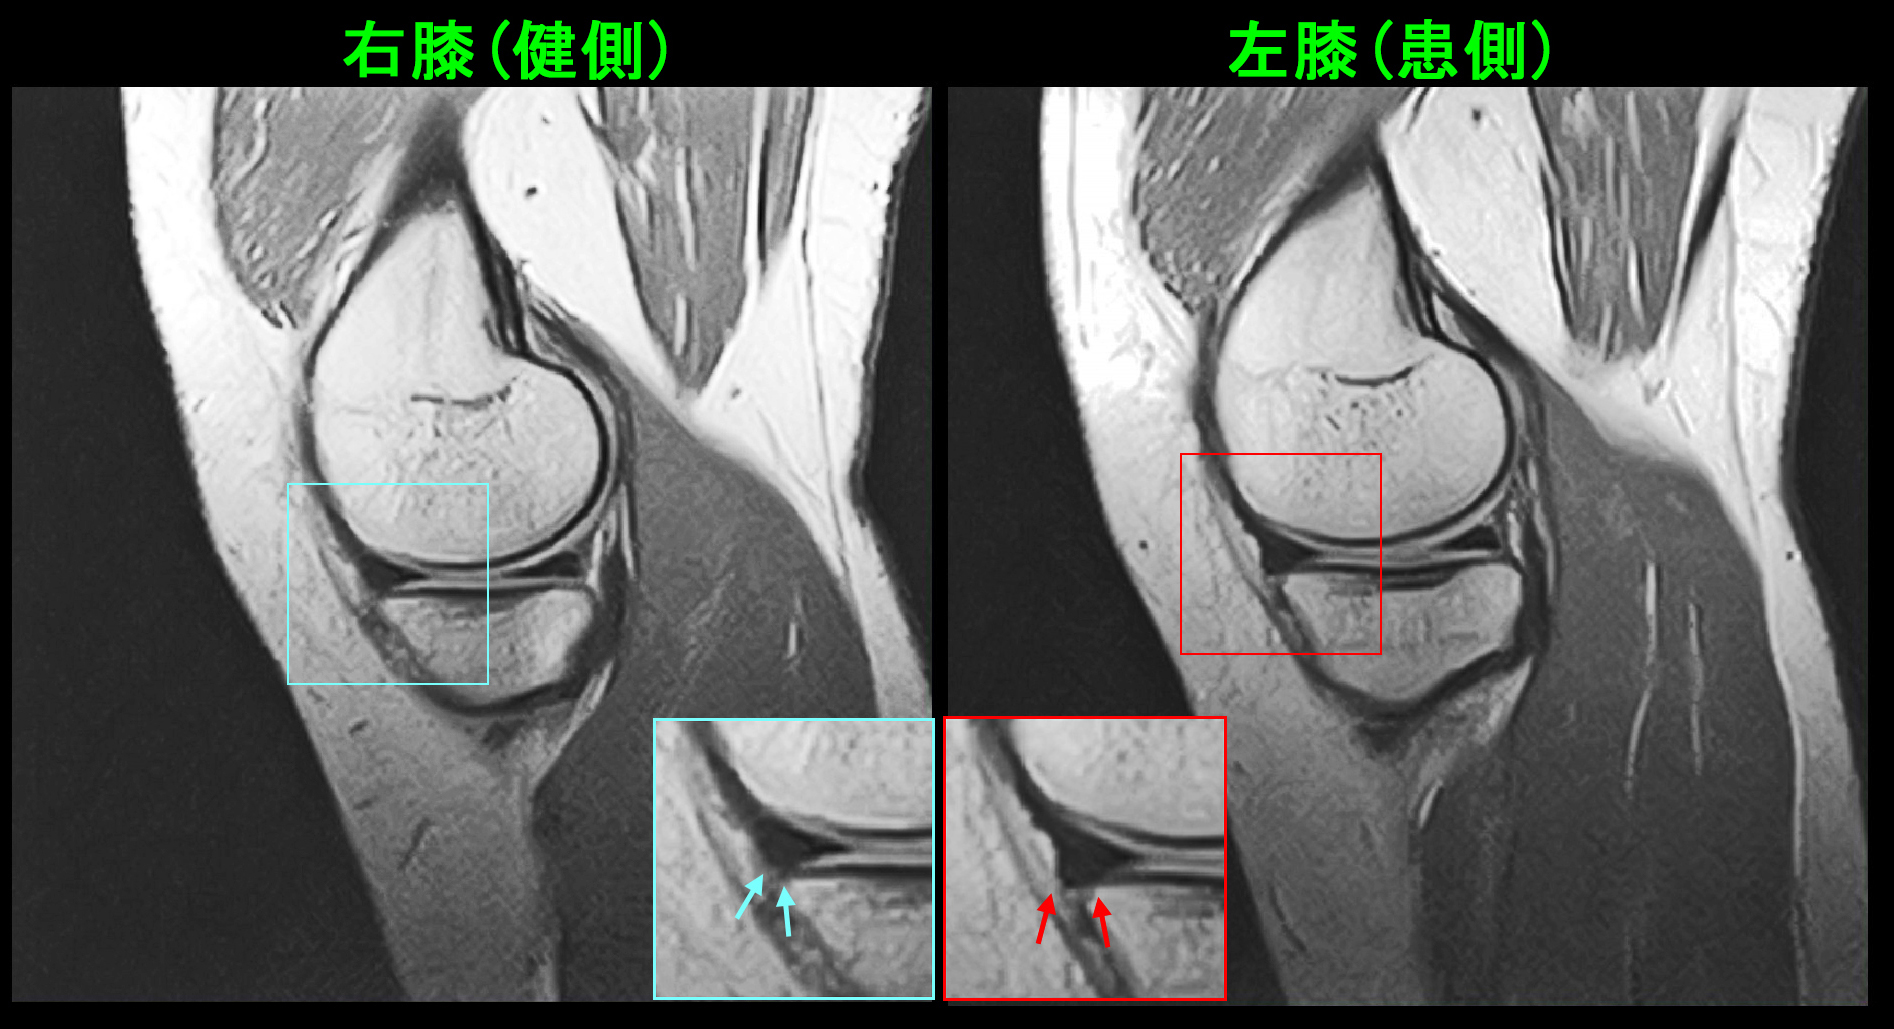

18才の高校3年生の女子生徒です。令和7年9月6日自転車での学校帰りに同じ方向に走っていた車が左折してきて、それを避けようとして左側に転倒し、左膝を打撲しました。9月7日他整形外科受診して、打撲の診断でシップと投薬を受け、服薬は有効だったそうですが、服薬終了で左膝痛は悪化したそうです。以後時々左膝痛があり、10月12日さらに症状は悪化し、左膝屈曲で痛み、椅座位でも痛みがあるということで、10月25日に当院を受診されました。しかし、卓球での痛みはVAS4というので大したことないという印象でした。

18才女 MR1.jpgPDの冠状断の左膝の中央部分では軽度の亜脱臼を認める所見でした。この内側半月板所見は注意深く観察しなければ、見落としても仕方ないような所見です。

18才女 MR3.jpg

PDの矢状断(横から見た所見)でも左半月板前方部は軽微な亜脱臼を示していました。この程度の亜脱臼の所見ならば、服薬で良くなるであろうと推察し、鎮痛剤のロキソニン2錠とプレドニン2.5㎎2錠を朝夕で1週間、2週目は鎮痛剤のメロキシカム1錠とプレドニゾロン2.5㎎朝1錠で対応しました。40代50代の加齢性の症状でもこの薬剤の服用で症状は軽減することが多くあります。